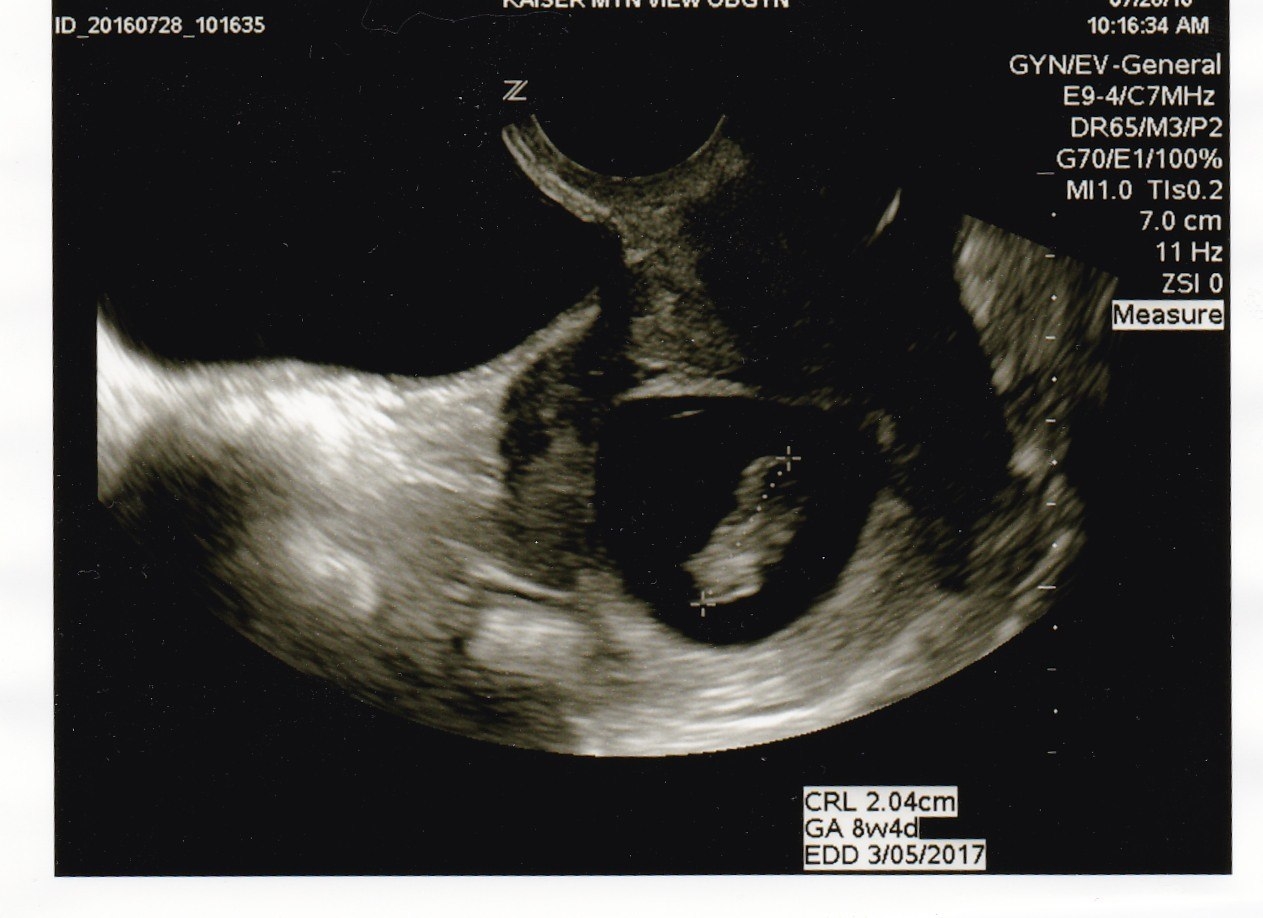

Here is Baby Rick at 8w4d measuring in at 9w0d at our US last Thursday! The little one was swimming around and moving those arms and legs! It was amazing to see as first time parents. Can't wait to see him/her again in a little over 5 weeks